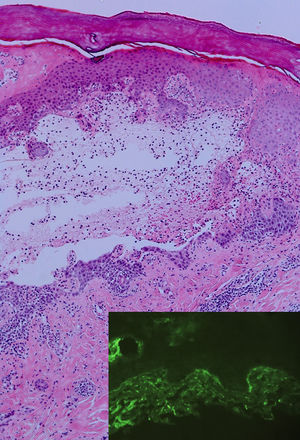

Una mujer sana de 33 años, en su segunda gestación de 35semanas con la misma pareja, comenzó con unas lesiones generalizadas y en la boca, sin referir procesos infecciosos previos ni nuevas medicaciones. En la exploración física se apreciaban unas placas eritemato-edematosas, grandes, periumbilicales y en el cuello. En las palmas y en las plantas se apreciaban unas lesiones en forma de diana tipo eritema exudativo multiforme. En las mucosas orales yugales presentaba erosiones extensas sin vesículas ni ampollas (fig. 1). En la biopsia cutánea se apreció la presencia de una ampolla subepidérmica con espongiosis eosinofílica, sin degeneración vacuolar de la membrana basal epidérmica (fig. 2). En la inmunofluorescencia directa se apreciaban depósitos lineales focales de C3 en la membrana basal. En la inmunofluorescencia indirecta los anticuerpos anti BP-180 fueron negativos. La serología para Mycoplasma pneumoniae fue negativa para IgM e IgG. Se inició corticoterapia oral con prednisona a dosis de 0,75mg/kg/día y tópica con propionato de clobetasol al 0,05% en crema. Las lesiones fueron mejorando progresivamente hasta su desaparición 2meses después del parto y dejando pigmentación residual. En el momento del parto el bebé nació sin lesiones cutáneas ni otras complicaciones como parto prematuro o bajo peso. Tras un seguimiento de 6meses la paciente no volvió a presentar lesiones.

Los hallazgos histológicos dependen del momento evolutivo y de la intensidad de las lesiones. La presencia de abundantes eosinófilos es un hallazgo constante en el penfigoide gestacional. En la fase de ampollas, la condición sine qua non es la presencia de una ampolla subepidérmica en la membrana basal. En la inmunofluorescencia directa, la presencia de depósitos de C3 de forma lineal a lo largo de la membrana basal se observa en el 100% de los casos. Los depósitos de IgG, subclase IgG1, se observan en el 25-30% de los casos. En la inmunofluorescencia indirecta, dependiendo de la técnica empleada, entre el 30-100% de los casos pueden detectarse anticuerpos IgG contra el antígeno BP-180, pero no siempre los títulos se correlacionan con la actividad de la enfermedad.